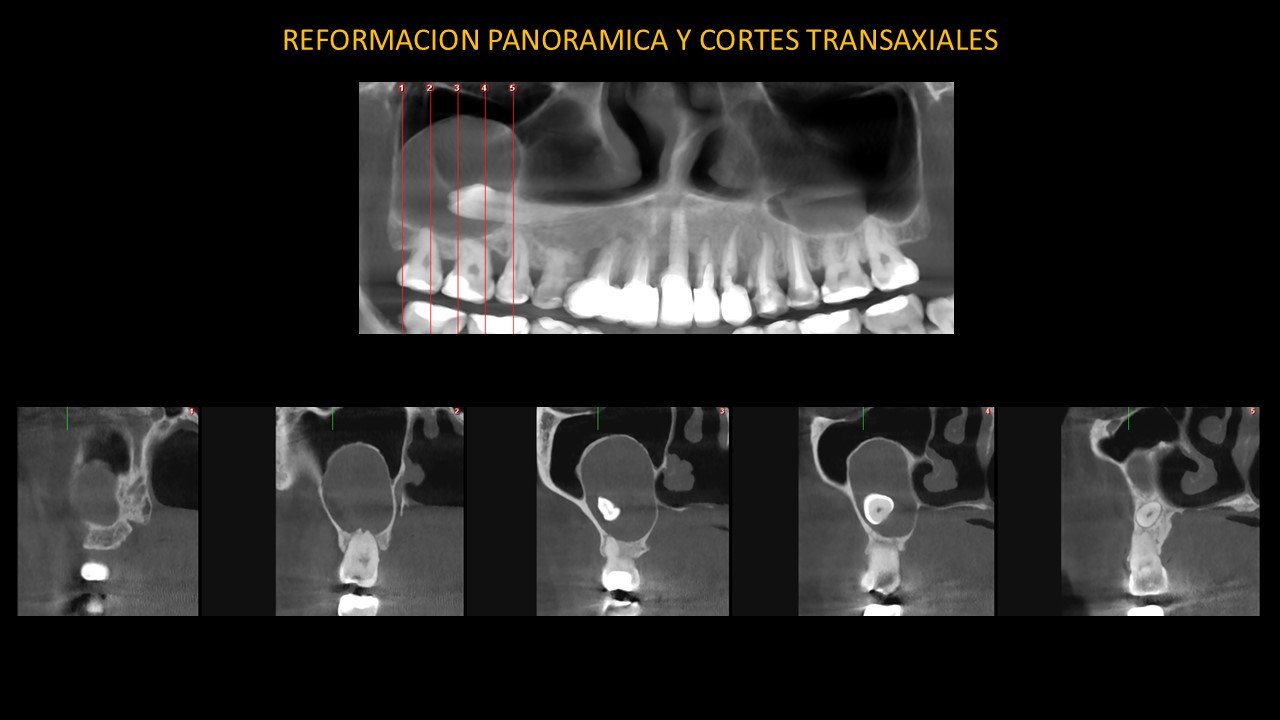

Figura 5

En las vistas transaxiales (Figura 5), observamos la reabsorción radicular externa de las piezas 17, 16 y el adelgazamiento y la erosión parcial de la pared lateral del seno maxilar derecho; el adelgazamiento y expansión de la tabla ósea palatina.